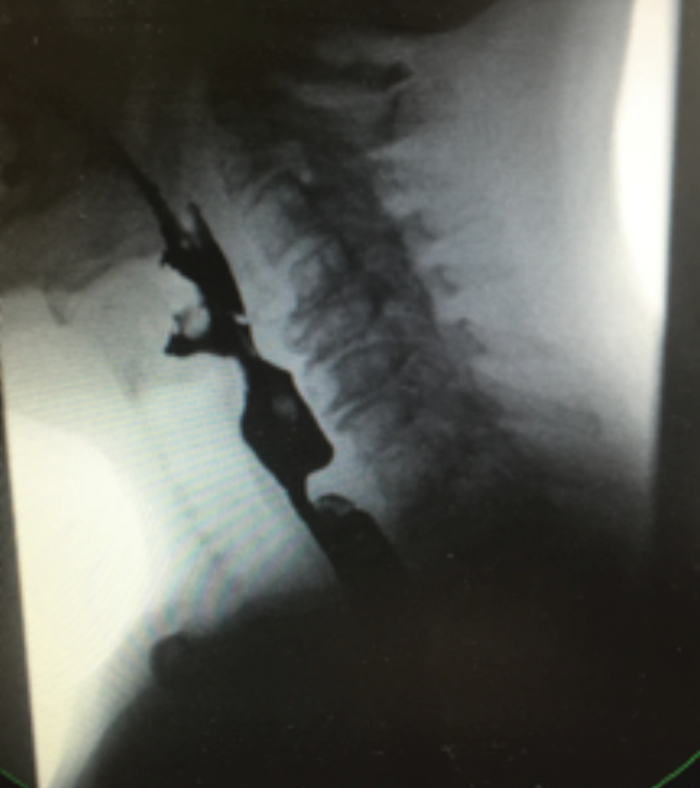

Transnasal oesophagoscopy (TNO) and balloon dilatation under a local anaesthesia

Many of us are becoming more and more familiar with the use of transnasal oesophagoscopy. It has a number of well-described uses in the outpatient setting and is well tolerated by our patients. Yakubu Karagama describes taking this technique a...